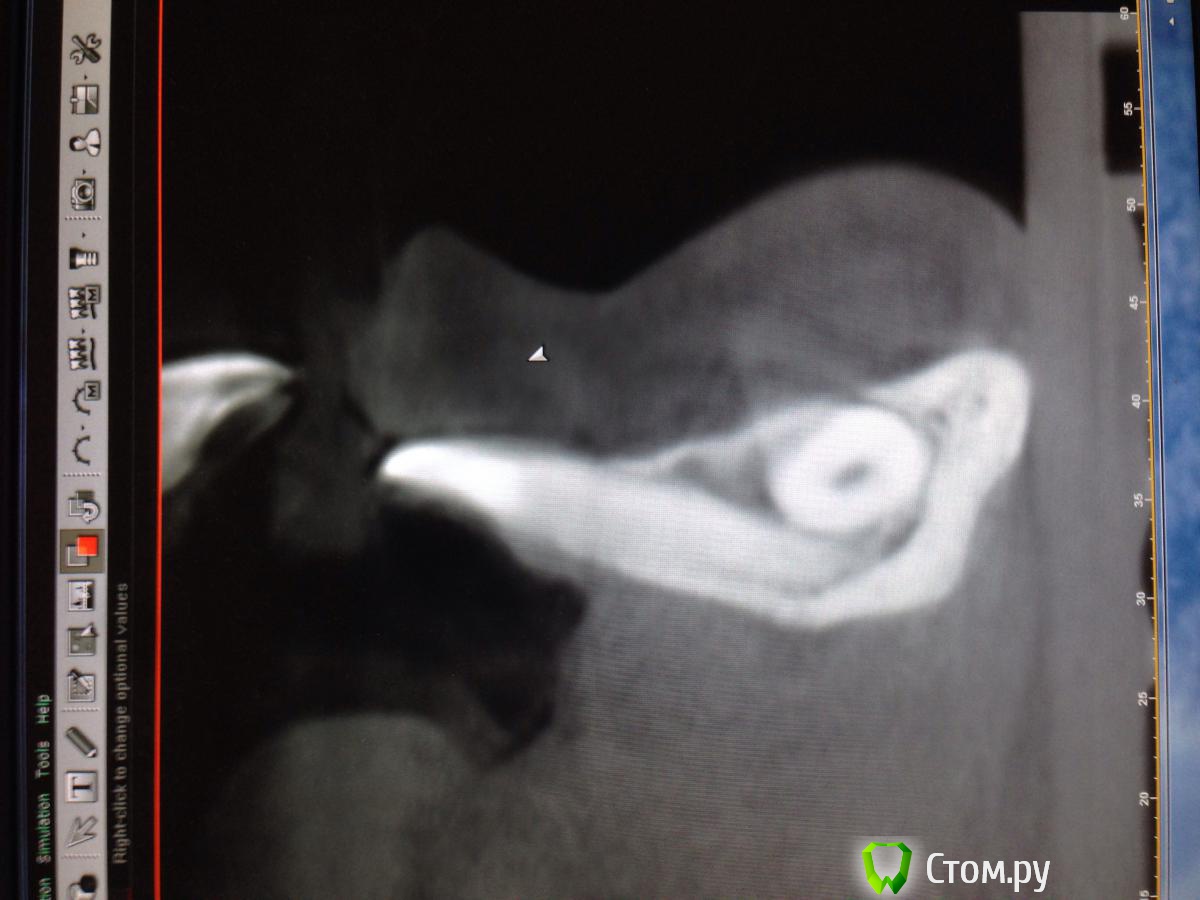

Opimar Опубликовано 29 ноября, 2013 Поделиться Опубликовано 29 ноября, 2013 Прошу совета по тактике лечения. Ортодонты привели пациента, 43 надо удалять. Впринципе ничего такого я не вижу, но все-таки как грамотно поступить взяться амбулаторно или направить в стационар. План лечения: Внутрибороздковый пошире с отслойкой передней поверхности подбородка ну и бор машиной фрагментировать зуб и удалить, либо без фрагментации если так пойдет. Швы, антибиотики, холод. Ну и предупредить о возможном онемении и травме резцов. Ссылка на комментарий

Alexey Doc Опубликовано 29 ноября, 2013 Поделиться Опубликовано 29 ноября, 2013 Амбулаторное удаление.Вот только дизайн разреза нужно првильный выбрать!не думаю что втутрибороздковый разрез создаст условия для оптимального доступа, да и отслойка при нем будет на большой площади. я бы сделал линейный ниже уровня переходной складки , если он не будет проходить над планируемым костным дефектом. 3 Ссылка на комментарий

kriokov Опубликовано 29 ноября, 2013 Поделиться Опубликовано 29 ноября, 2013 Разрез послойный:сперва слизистую в области переходной, затем мышцы (ушивание в обратной последовательности). Отверстие на уровне (приблизительно) средины корня. Три сегмента.Удаляете средний, дальше по ситуации.В дефект-от коллагена до графта.Давящая повязка снаружи.если доктор не делал низких доступов, трудно будет сообразить по первой как ушиться. Может уж чуть выше разрез сделать по нижней границе прикрепленной если прикрепленной хватает? И риск рецессии меньше чем при сулькулярном, и одним блоком надкостницу с мышцами поднимет, и ушьется почаще но в один слой, и ветки ментального в мягких тканях если чего целые будут.? 3 Ссылка на комментарий